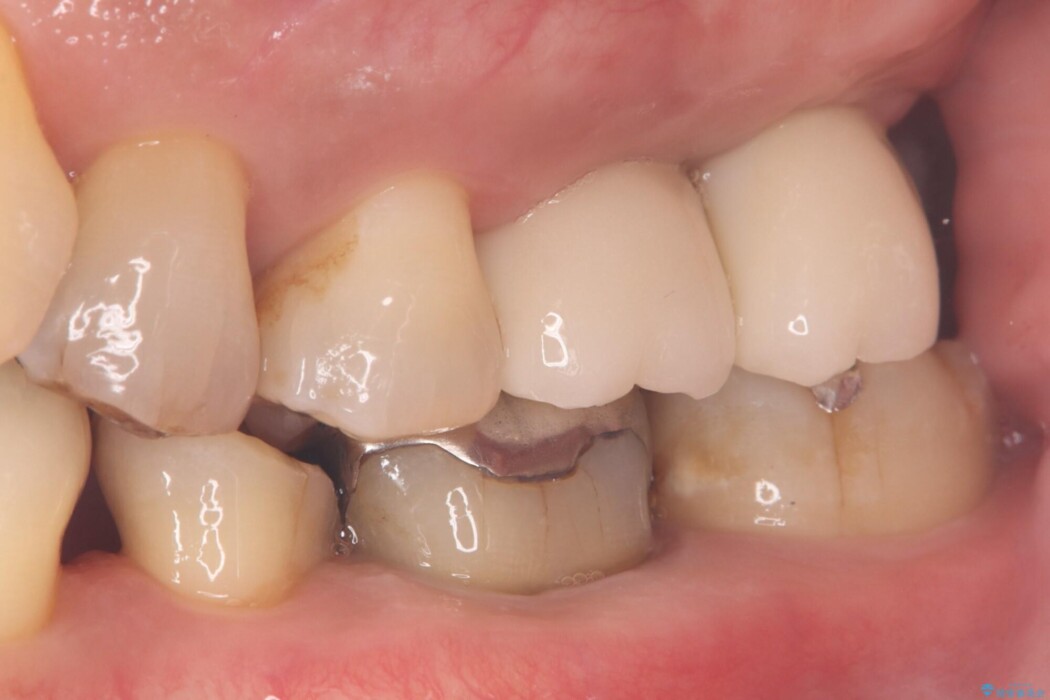

左上奥歯の欠損を、抜歯即時埋入を活用したインプラントで修復しました。

精密な位置決めと効率的な術式により、短期間でしっかり噛める喜びとお口全体の健康なバランスを取り戻すことができました。